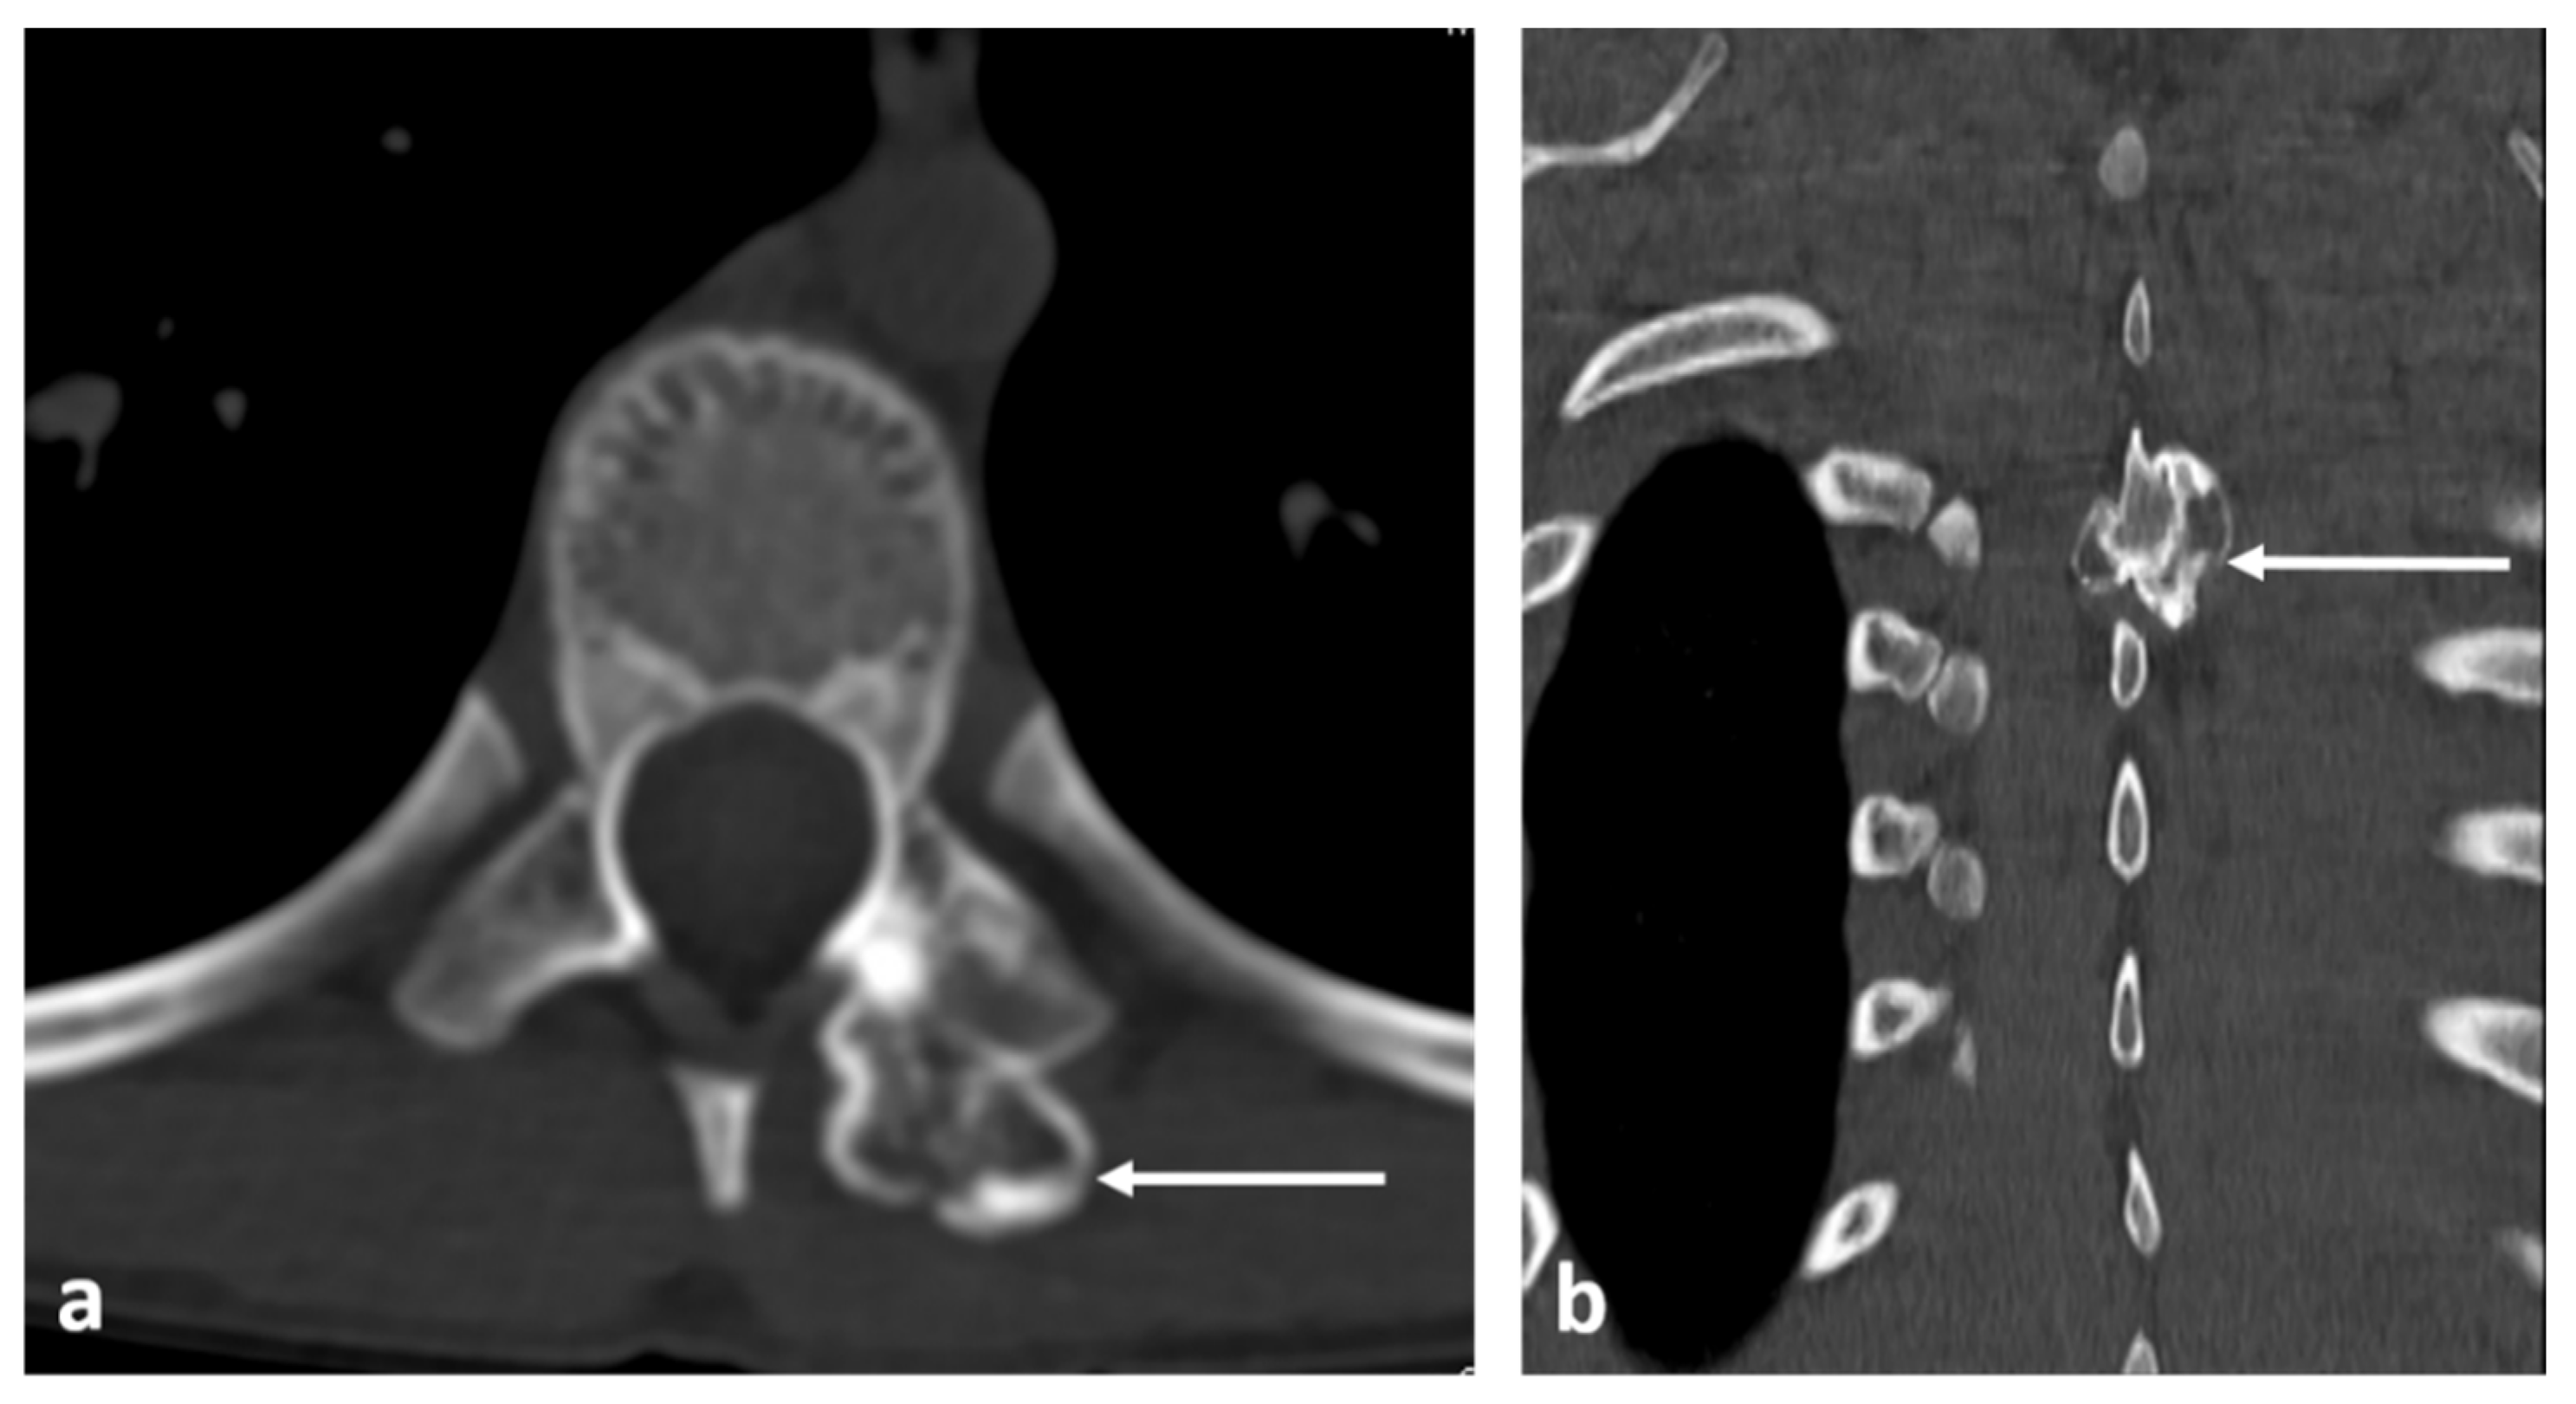

| Haemangioma | Honey comb appearance. ‘Corduroy’ and ‘polka dot’ signs. | Usually T1 and T2 hyperintense due to fat content. Signal drop out >20% on out of phase chemical shift imaging. |

| Benign notochordal tumour | Midline lesion in the body. Sclerosis or trabecular thickening typically, but lysis can be present. | Low T1 and high T2 signal. No enhancement. |